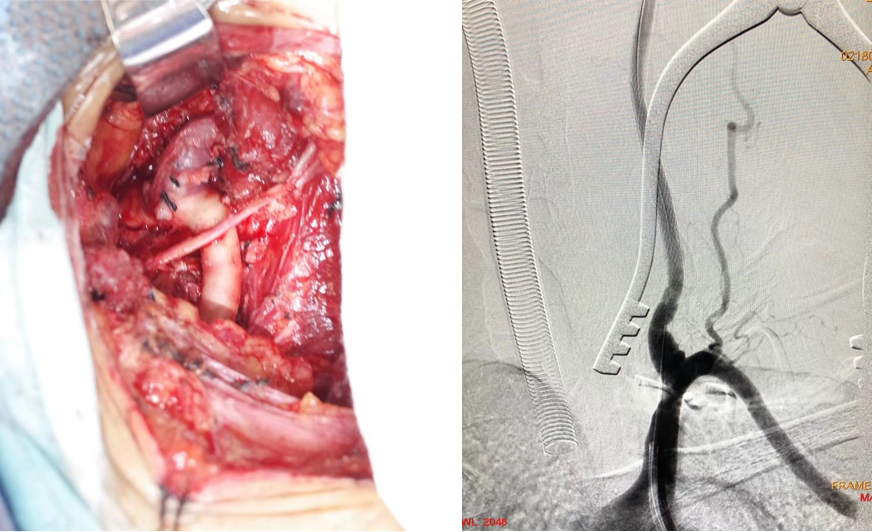

M,60,左侧小脑梗死,左椎动脉V1-V2段长段闭塞

椎动脉外翻剥脱、椎动脉-锁骨下动脉端侧吻合

椎动脉-锁骨下动脉端侧吻合

介入开通